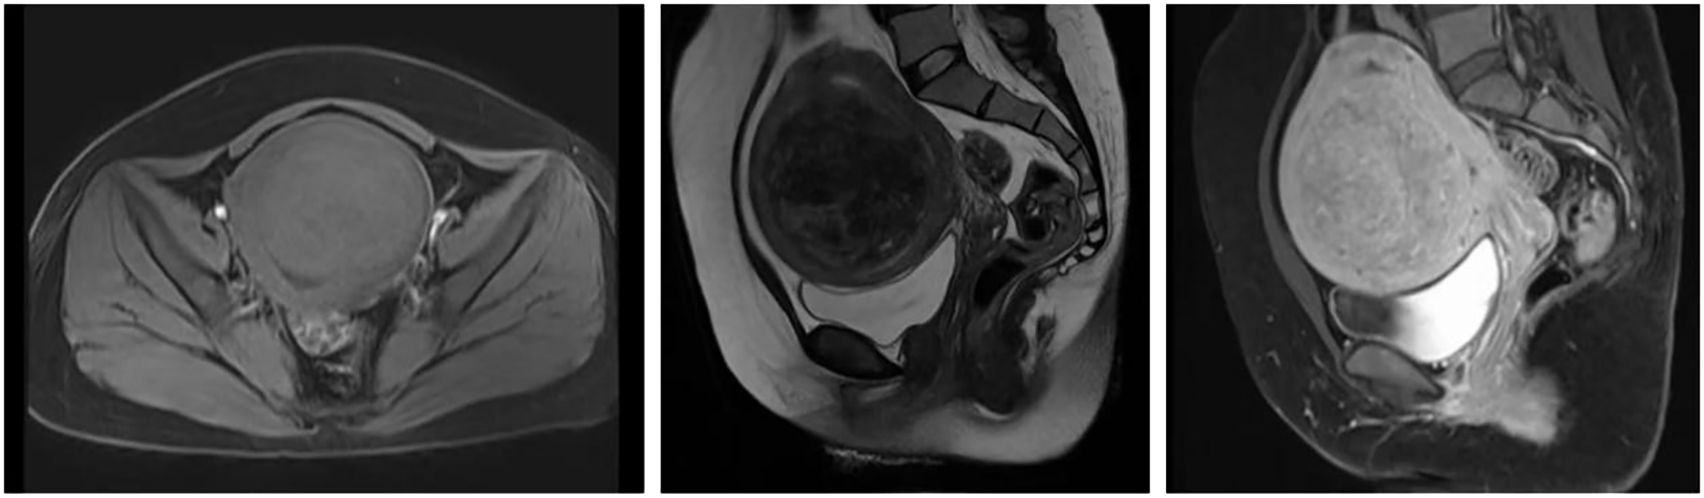

Background: High-intensity focused ultrasound (HIFU) ablation is widely regarded as a safe and minimally invasive technique for treating uterine fibroids. However, severe complications such as uterine rupture and septic shock remain exceedingly rare. Case presentation: We report a case of a 42-year-old woman who developed uterine rupture complicated by septic shock one month after undergoing HIFU ablation for uterine fibroids. Conclusions: Although HIFU ablation for uterine fibroids is widely considered a safe and minimally invasive procedure, clinicians should recognize the potential for severe complications, including uterine rupture and septic shock.